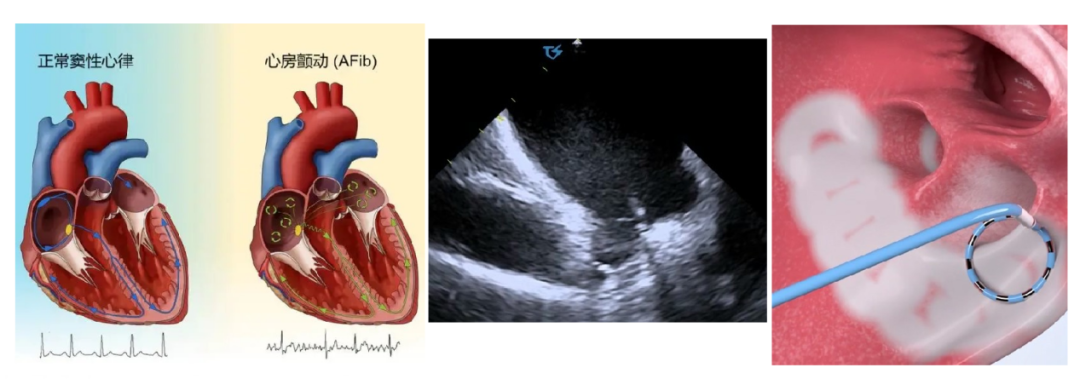

手术过程中,蓝主任借助三维系统和心腔内超声导管的完美结合,首先通过血管插入超声导管,利用超声技术排除心房血栓和术前心包扫描,然后在心腔内超声指导下完成房间隔穿刺,构建左房通路,送入标测导管构建心脏的三维模型。然后在三维模型的指引下,将消融标测导管精确地送到心脏的特定部位,通过释放脉冲能量,成功消除患者心房内触发房颤的异常电位,患者恢复正常的窦性心律。整个手术在局麻下进行,手术过程极低射线,做到真正的安全绿色电生理,为患者的生命安全开通“绿色通道”,并且手术仅历时一小时左右,患者术中体验良好,术后恢复快,无不良反应。

心腔内超声导管引导下的脉冲消融是一种微创手术,通过在心腔内使用超声导管,医生能够实时监测和构建心脏的三维结构,精确地定位到引起房颤的异常电生理活动区域。这项技术的优势在于它能够在极低X射线的情况下,安全、准确地引导消融导管到达目标位置,同时房颤脉冲消融技术(PFA)脉冲电场消融术是房颤导管消融领域一种全新的安全、高效的治疗方法。其原理是通过高压脉冲电场,造成细胞不可逆的电穿孔,最终导致细胞程序性死亡。与传统的治疗方式相比,房颤脉冲电场消融安全性更高,具有一定的组织选择性,能显著减少心房食道瘘、肺静脉狭窄、心包填塞等并发症的发生风险。同时脉冲电场消融手术时间短、多点同时放电,每次放电仅需2-4秒,效率高,与其他消融方式相比,能将整体手术时间缩短一半,患者术中痛感减少,手术流程更简单,患者术后恢复更快,是房颤治疗的又一把利剑。